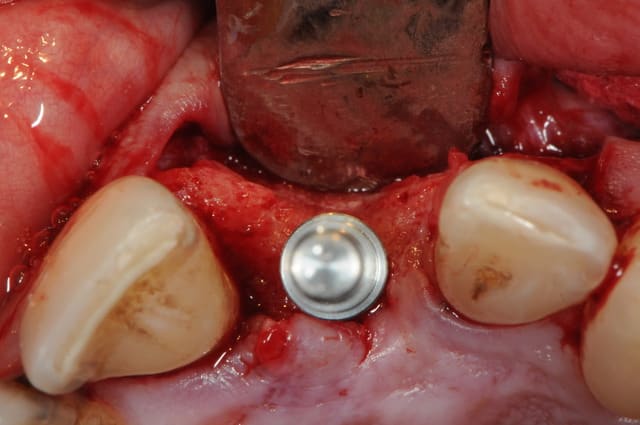

au cas où vous ne fait la provisoire immediatement, vous pouves choisir le" one stage procedure" . Dans ce cas, vous conservez la profile de la gomme avec une "gingiva former".

dans la zone estetique e tres important a fere extraction atraumatique e forage palatine pour preserver l os vestibularie.

le placement du implant doivent suivre( respecte) les règles de "3D insertion in estetic zone".

Un pilier de cicatrisation customisé ou personnalisé c'est une vis de ciatrisation individualisée : elle peut être faite de plusieurs facons par exemple à partir de ton porte implant que tu modifies par apport successif de composite.

Ca ressemble à cela :